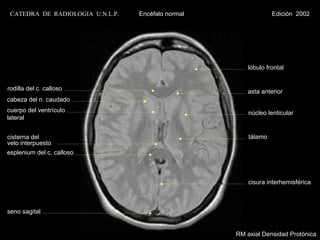

CATEDRA DE RADIOLOGIA U.N.L.P.   Encéfalo normal                Edición 2002

lóbulo frontal

rodilla del c. calloso                                 asta anterior

cabeza del n. caudado

cuerpo del ventrículo                                   núcleo lenticular

lateral

cisterna del                                            tálamo

velo interpuesto

esplenium del c. calloso

cisura interhemisférica

seno sagital

RM axial Densidad Protónica